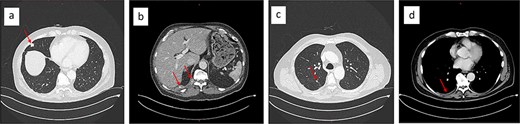

To address pain symptoms, radiotherapy to the right paravertebral mass was planned; however, due to a lack of response to treatment, a CT-guided biopsy of the site was performed before proceeding. Histological analysis revealed epithelioid neoplastic cells (Fig. 1a), which expressed CD31, CD34, and ERG on immunohistochemistry, indicating endothelial differentiation (Fig. 1b). Nuclear expression of CAMTA1 protein confirmed an EHE (Fig. 1c).

Core biopsy demonstrated a collagen-rich tumour with chondromyxoid stroma of low cellularity (a: haematoxylin and eosin (H&E) stain). The tumour cell expresses immunohistochemically the endothelial marker CD31 (b) and shows nuclear expression of CAMTA1 protein (c), diagnostic of an epithelioid haemangioendothelioma (EHE).